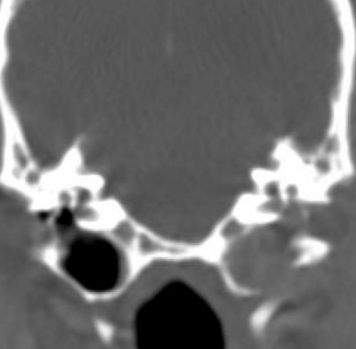

- ๋ฐฉ์ฌ์ , CT : concurrent otitis media, calcification, bone lysis (neoplasia)

์ด๋๊ฐ ๋ผ์ฒ๋ผ ๋ณด์.

์ผ์ชฝ tympanic cavity ๋ ์ ์ / ์ค๋ฅธ์ชฝ์ ๊ฝ ๋งํ ์๊ณ , ๋ผ๋ ์์.

์ค๋ฅธ์ชฝ์ ์ค์ด๋ก ๋์ด๊ฐ๊ธฐ ์ ์ ๋นจ๋ฆฌ ์กฐ์น ํ์ / ์ผ์ชฝ์ ์ค์ด๊น์ง ์ด๋ฏธ ์งํ / ๋๊ทธ๋ผ๋ฏธ๋ petrous temporal bone; lysis๊ฐ ์ผ์ด๋ ๊ฐํต์ฑ ์๋ ๊ฒ์ฒ๋ผ ๋ณด์ - ์ข ์ ์์ฌ